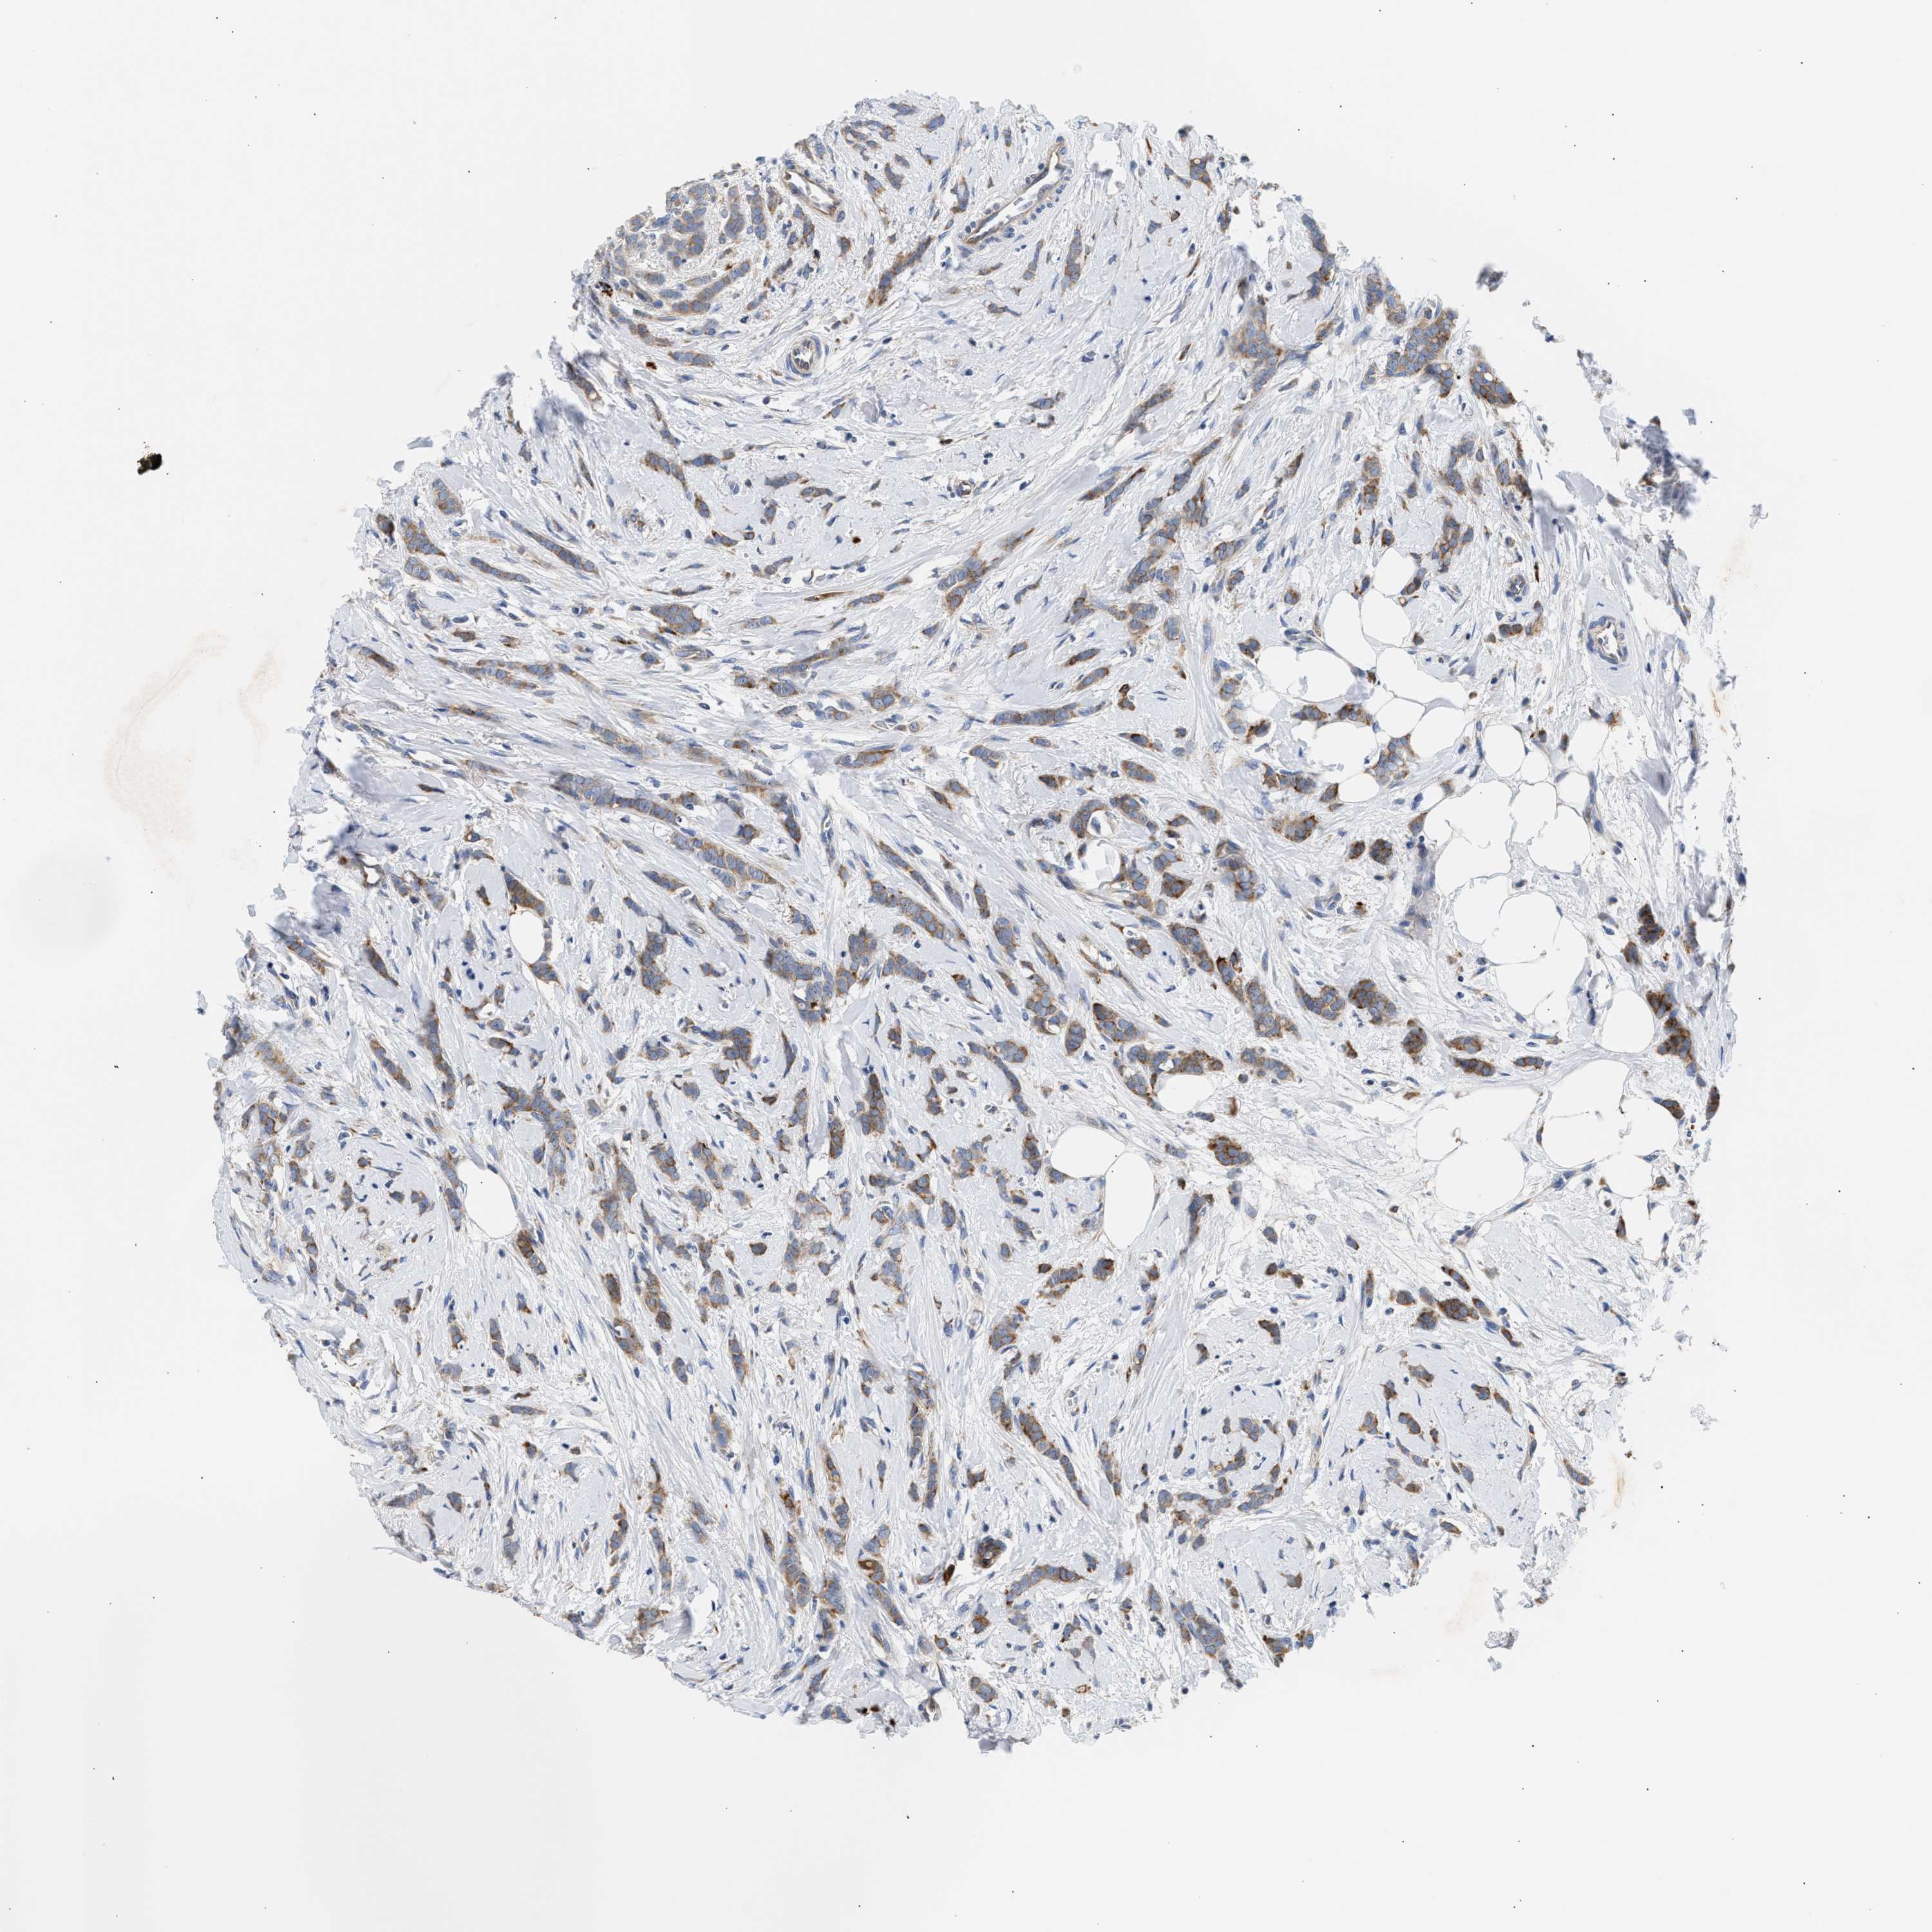

CANCER BREAST CANCER Show tissue menu

BRCA TCGA BRCA VALIDATION PROTEIN EXPRESSION

ANTIBODIES

AND

VALIDATION